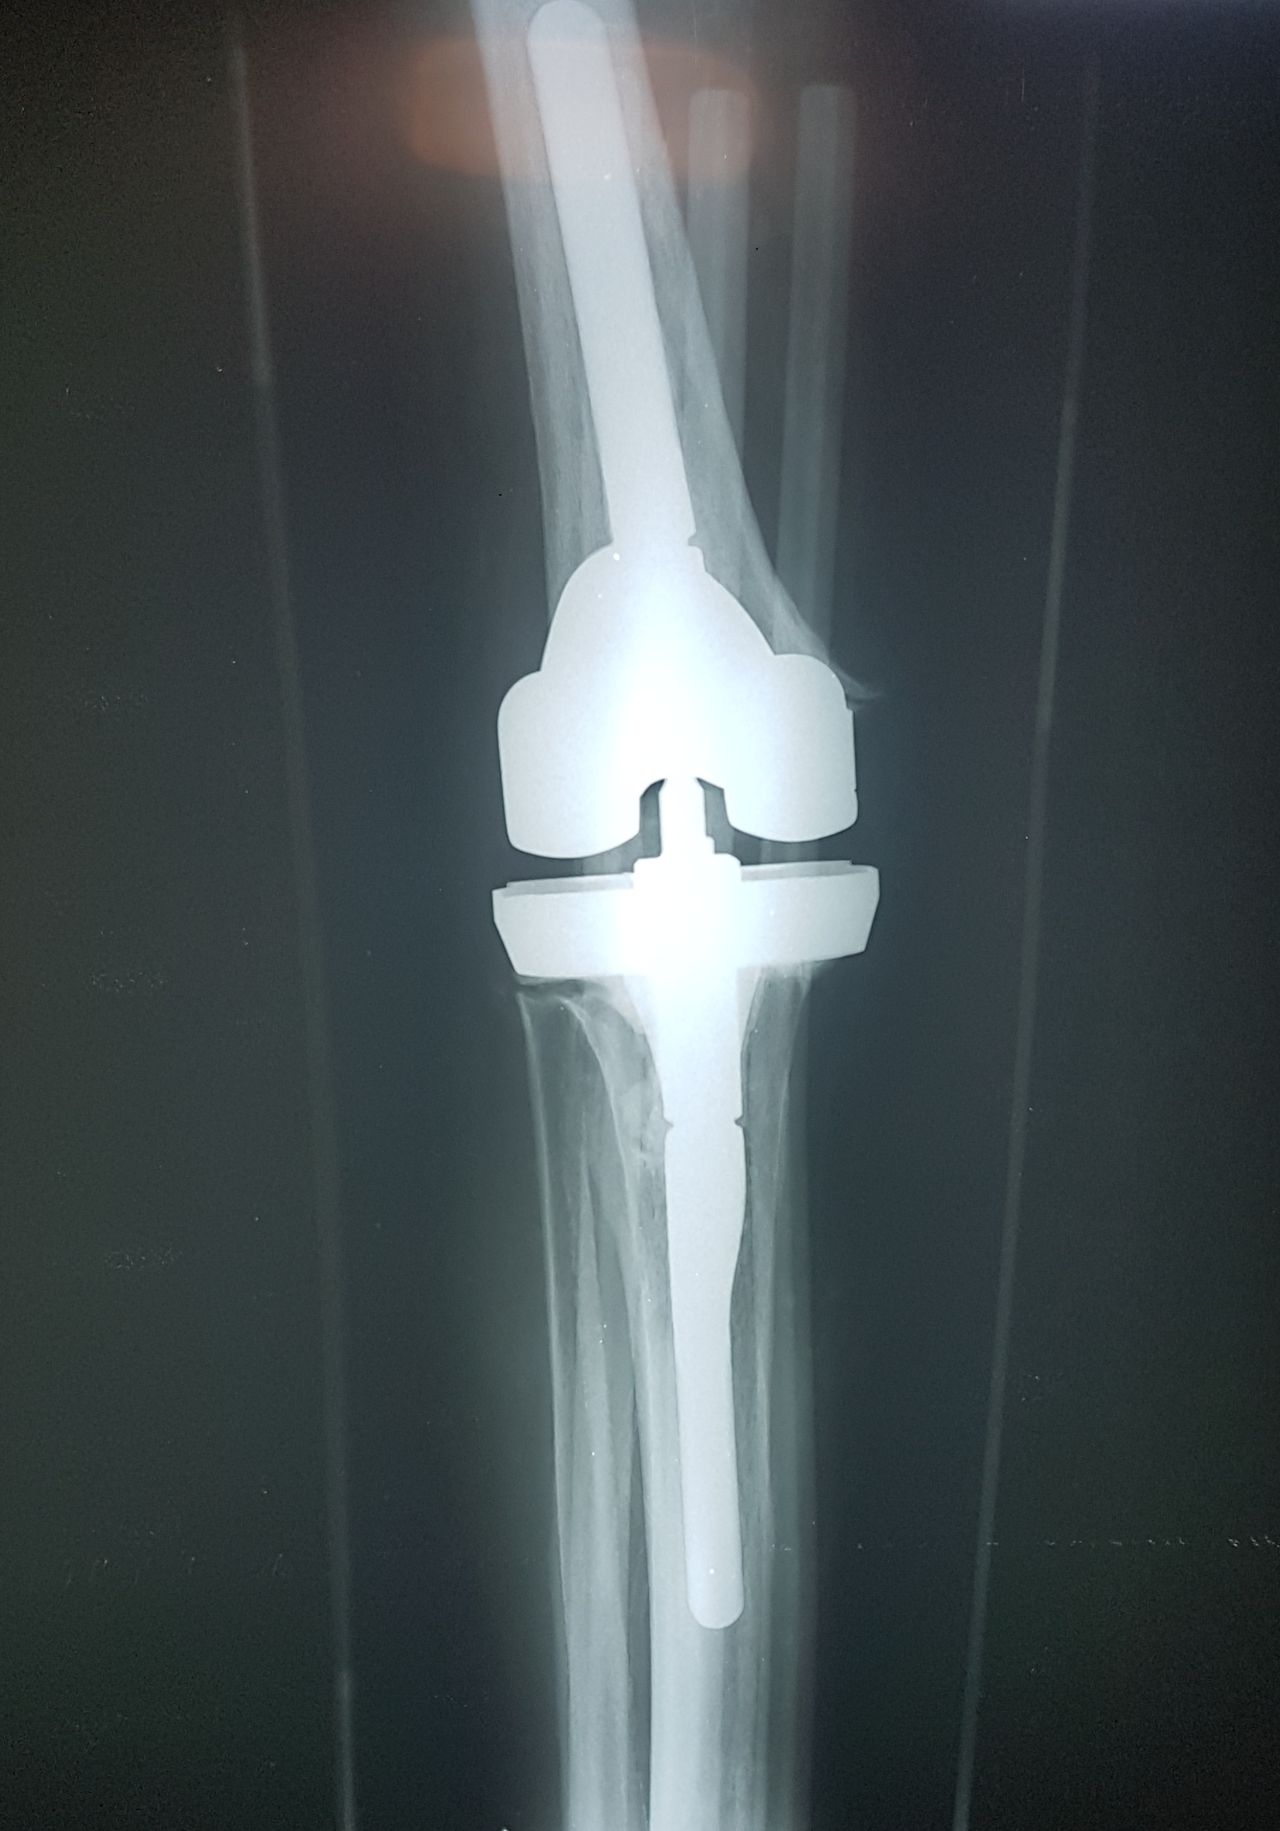

Soy   egresado  de  la  Universidad Autonoma de   Nuevo  Leon. especialidad de ortopedia y traumatologia  en    hospital  numero  21  del  IMSS ne Monterrey  N.L ,con entrenamiento en la  subespecialidad  de   reconstrucion  articular  y  artroscopia  que incluye  lesiones  de  meniscos  , reconstruccion de ligamentos cruzados , lesiones  condrales ,  gonartrosis   tengo  una  historia laboral    institucional de 30  años    hasta el 30  de lulio del 2024 estuve  10  años  en  el  modulo  de  artroscopia  con aproximadamente   1120    artroscopias  de rodilla   y  15 años  en  el  departamento  de    artroplastia  de rodilla  o  de  reemplazos  articulares   ,  los  ultimos   15  años    como profesor  adjunto   y titular  en los cursos    de pre  y posgrados  de  traumatologos  en la  subespecialidad  de  con aproximadamente   160 cirugias  institucionales    en   artroplastia de  rodilla    por  cada año   y  un  numero menor en el  medio particular  dando un total  aproximado  de  2,560  cirugias . de  estas  el  10%    de  revision  y  5%  preotesis    tumorales    de  actualmente   en  funciones  en  el  medio privado  y  acreditado  en todos los  hospitales  de la  localidad  y  con todas  las  aseguradoras   de  gastos  medicos .

Excelente doctor, el mejor, me ayudó con el problema que tenía un tumor en el hueso de mi rodilla, recuperé mi vida después de ese difícil proceso…